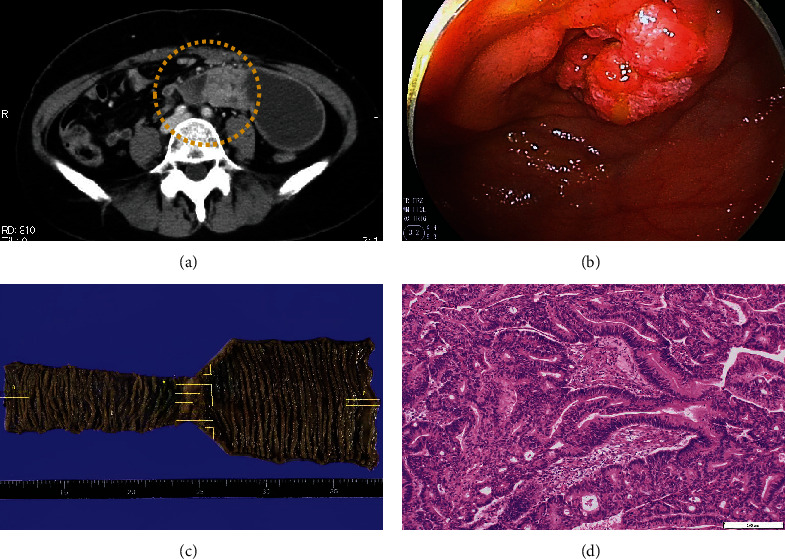

从生殖器外部位转移到子宫的情况非常罕见。我们介绍了一例女性病例,她曾接受过小肠癌手术,随后出现左侧卵巢和子宫转移。一名 50 多岁的无子宫妇女因患小肠癌接受了腹腔镜小肠部分切除术和淋巴结清扫术。五个月后,计算机断层扫描(CT)发现左侧卵巢肿瘤和腹水。她接受了双侧附件切除术和辅助化疗,卵巢肿瘤被诊断为小肠癌转移。小肠癌手术两年后,正电子发射断层扫描(PET)-CT 扫描发现子宫积液。宫颈细胞学检查未发现上皮内病变或恶性肿瘤。子宫内膜组织学检查显示为子宫腺癌。患者接受了全腹子宫切除术,随后接受了辅助化疗。子宫肿瘤的组织病理学和免疫组化结果显示,这是一种小肠癌转移瘤(细胞角蛋白7 [CK7] [-]、细胞角蛋白20 [CK20] [+]、特殊AT-富序列结合蛋白2 [SATB2] [+]、配对盒基因2 [PAX2] [-]和雌激素受体[ER] [-])。对于癌症患者来说,组织病理学和免疫组化对于区分原发性和转移性肿瘤以及指导治疗方案的选择非常重要。

Uterine metastases from extragenital sites are rare. We present a case of a woman who had undergone surgery for small intestinal cancer and subsequently developed metastases in her left ovary and uterus. A nulliparous woman in her 50s underwent laparoscopic partial small bowel resection with lymph node dissection for small intestinal cancer. Five months later, computed tomography (CT) revealed a left ovarian tumor and ascites. She underwent bilateral adnexectomy and adjuvant chemotherapy, and the ovarian tumor was diagnosed as a small intestinal cancer metastasis. Two years after the small intestinal cancer surgery, a positron emission tomography (PET)-CT scan revealed a uterine accumulation. Cervical cytology was negative for intraepithelial lesion or malignancy. Endometrial histology showed an adenocarcinoma of the uterus. The patient underwent total abdominal hysterectomy followed by adjuvant chemotherapy. Histopathology and immunohistochemistry of the uterine tumor revealed that it was a metastasis of small intestinal cancer (Cytokeratin 7 [CK7] [-], Cytokeratin 20 [CK20] [+], Special AT-Rich Sequence-Binding Protein 2 [SATB2] [+], Paired Box Gene 2 [PAX2] [-], and estrogen receptor [ER] [-]). In patients with cancer, histopathology and immunohistochemistry are important for distinguishing between primary and metastatic tumors and for guiding the choice of treatment.